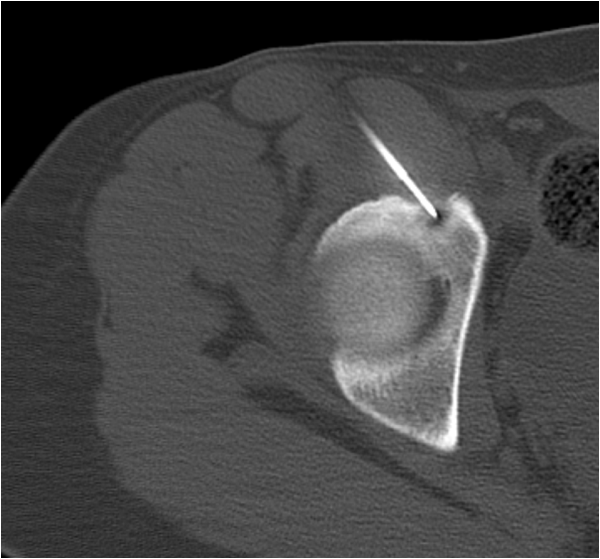

CT is also used to guide therapeutic interventions like bone biopsy, vertebroplasty or radiofrequency ablation of certain bone tumors.

Fig. 5. Osteiod osteoma of the acetabulum in a 14-year-old girl with persistent hip pain. A radiofrequency needle is positioned in the nidus of the osteoma. The patient was painfree immediately after successful thermoablation.